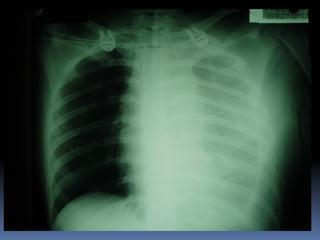

Abnormal Findings Un equalityof chest movement Dullness on percussion Decrease air entry Tachypenic heamothorax chest tube

heamothorax

chest tube